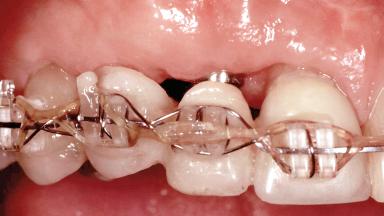

In 2001, a 48-year-old woman presented at a dental clinic with a failing fixed partial denture spanning from teeth 13 to 21. She was experiencing pain upon function, tenderness to palpation facial to tooth 13, and severe mobility of the prosthesis. Radiographic and clinical assessment revealed a subcrestal fracture of tooth 13, making its restoration unlikely. It was determined by the clinician that the tooth needed to be extracted prior to proceeding any further with dental care. After the extraction, the patient lost confidence in the progression of her treatment and sought consultation at the Center for Implant Dentistry. At her consultation visit in our clinic, an extra- and intraoral clinical examination revealed a medium lip line at full smile and an edentulous area spanning from 13 to 12 with both vertical and horizontal deficits in hard and soft tissue.

Type of Implants One-Piece|Reduced-Diameter

Prosthesis Type FDP

Loading Protocol Conventional or early

Retention Cemented, with prosthesis margin < 3mm submucosal Cemented, with prosthesis margin < 3mm submucosal

Provisional Implant-Supported Prosthesis Prosthodontic margin >3 mm apical to mucosal crest Prosthodontic margin >3 mm apical to mucosal crest

Interim Prosthesis during Healing Fixed Fixed